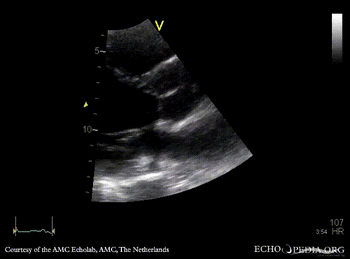

M-Mode through aortic valve: no opening of aortic valve PSAX